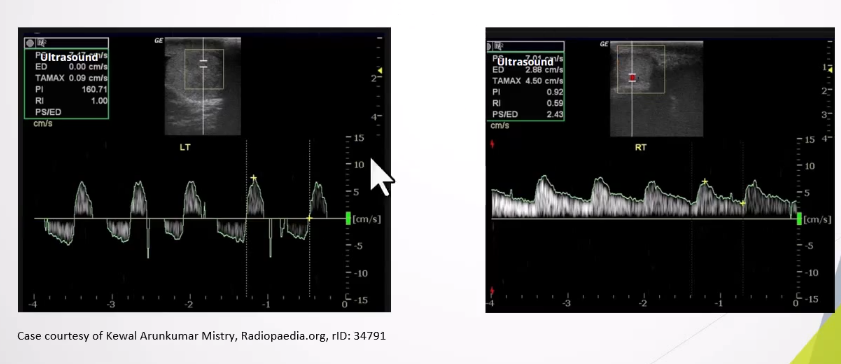

Altered Blood Flow:

Intratesticular arteries characteristically have a low resistance pattern with a mean resistive index of 0.62 (range 0.48 - 0.75)

Incomplete torsion - reversal of distolic flow and RI >0.75

Complete torsion - absence of blood flow in both the testis and epididymis

.